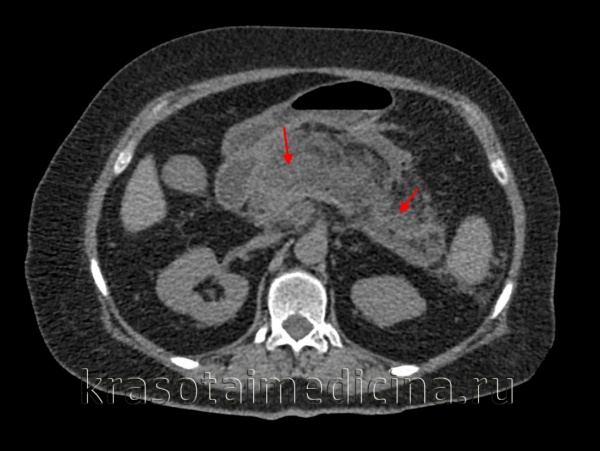

КТ органов брюшной полости. Множественные кальцинаты в области хвоста и тела поджелудочной железы (последствия множественных острых эпизодов панкреатита)